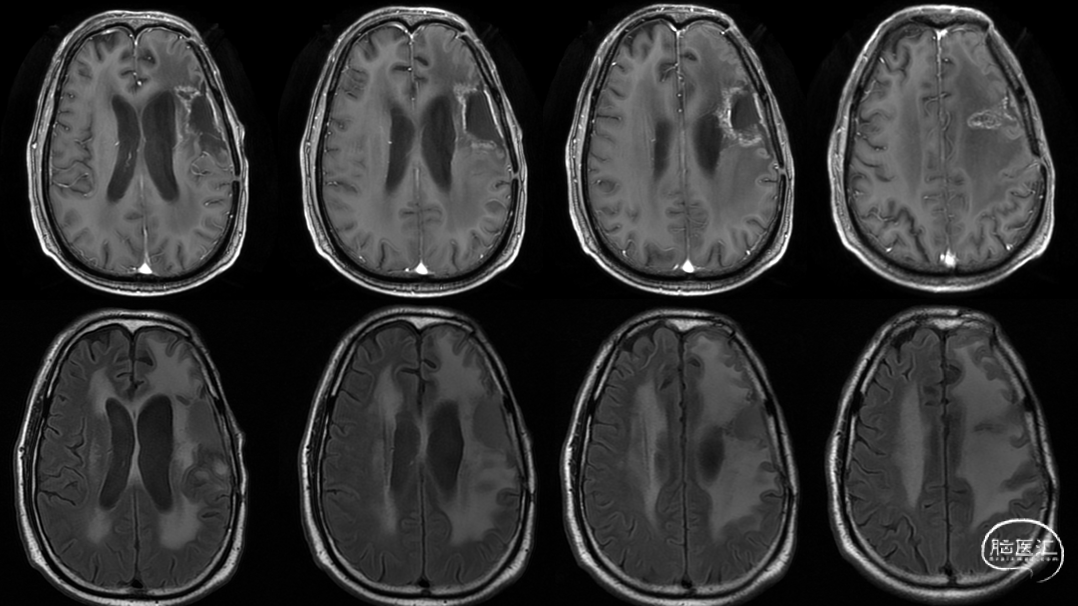

放疗后17月(2021-12-20)MRS显示左颞叶感兴趣区Cho/NAA约1.19-5.53:图示。

放疗后17月(2021-12-20)PWI显示感兴趣区脑血容量及血流量较对侧高低不一,平均通过时间及达峰时间延长,提示左侧病变区血流灌注降低:图示。

再次经MDT讨论,考虑假性进展可能,继续肿瘤电场治疗。

术后5周开始实施标准的新STUPP方案的辅助治疗,即在同步放化疗后,辅助替莫唑胺化疗的同时使用了电场治疗。目前生存25月,且临床和影像学表现均提示稳定,未见复发迹象。期间,在放疗后7月时复查MRI提示异常FLAIR信号区增大,经我院MDT讨论,考虑到强化信号减轻,无明显占位效应,患者无症状体征,考虑是治疗后水肿,非进展,故继续按原方案治疗。放疗后17月复查MRI出现术区边缘局部强化范围稍增大,但PWI示强化区局部呈低灌注且未见弥散受限表现,MDT讨论考虑为假性进展,继续原方案治疗。后续复查MRI强化范围减轻,证实了MDT的判断证实疾病稳定。患者生存时间已达25个月。全程安全顺利,仅出现一过性轻度皮肤反应。

辅助TMZ治疗过程中每2-3月复查MRI。治疗中曾出现水肿范围增大,尽管有部分区域弥散受限和MRS异常及血流量增加,但是临床症状未加重,仍继续原方案治疗,后续监测PWI显示病变区灌注减低。提示持续肿瘤电场治疗可以使病变长期稳定。此患者每天佩戴肿瘤电场治疗时间接近22小时,中间出现头皮发红和小水泡,经局部外用皮质类固醇和外用抗生素,暂停2天治疗恢复。至今随访25月稳定。说明肿瘤电场治疗联合TMZ治疗较单TMZ治疗明显延长胶质母细胞瘤患者PFS及OS,临床应积极推广使用。